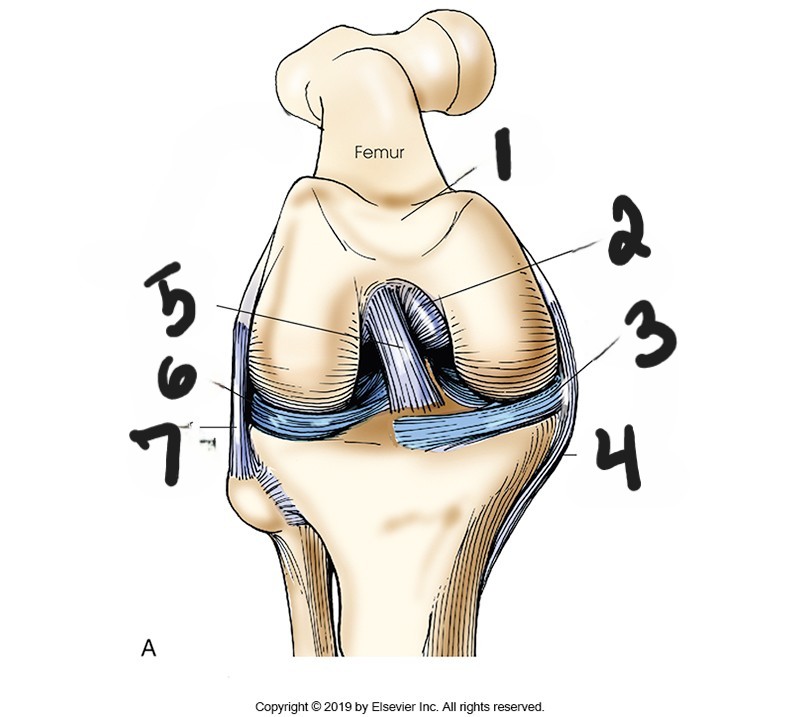

what is #1?

posterior cruciate ligament

what is #2?

medial meniscus

what is #3?

tibal collateral ligament

what is #4?

anterior cruciate ligament

what is #5?

lateral meniscus

what is #6?

fibular collateral ligament

what is #7?